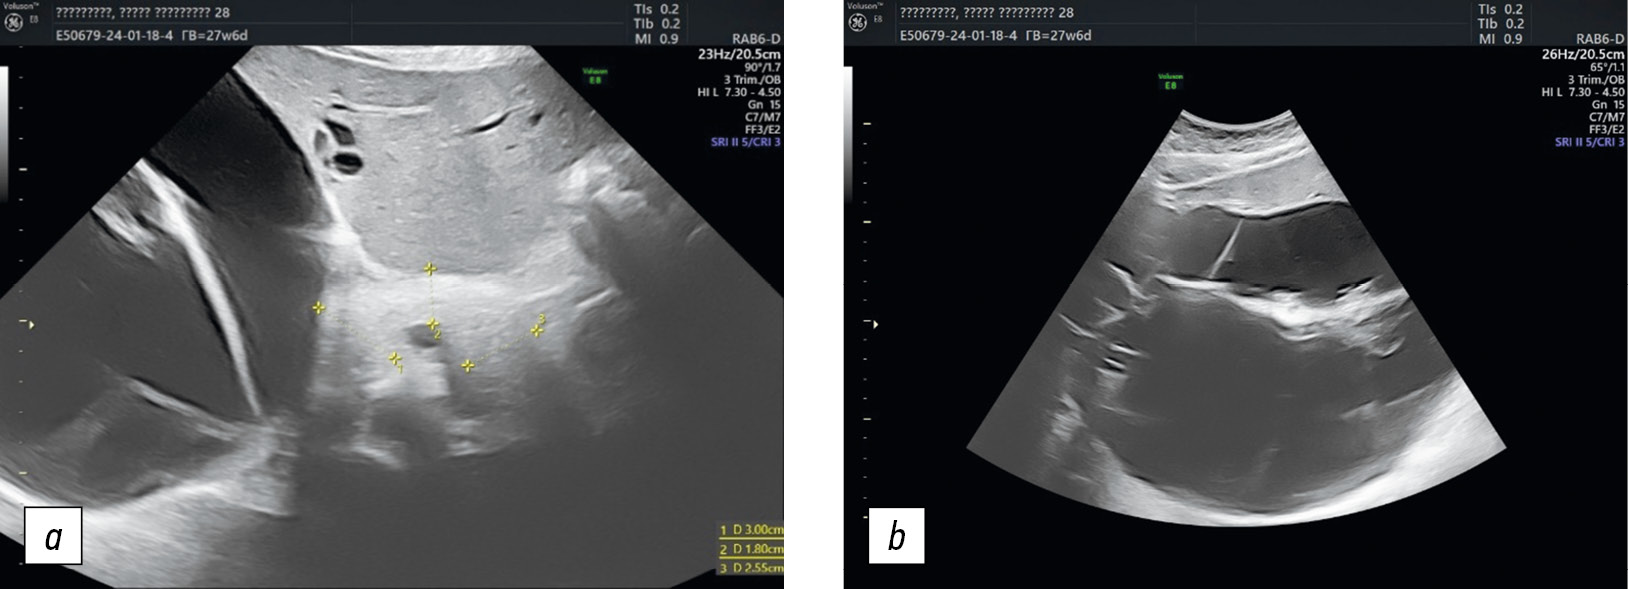

Выполнено повторное ультразвуковое исследование в стационаре. У правого верхнего угла матки, в области ворот печени определено многокамерное анэхогенное образование размером 219 × 160 × 175 мм, объемом 3207 см3, с четкими ровными контурами, толщиной стенок от 2 до 8 мм. Образование деформирует правую долю печени (рис. 1). В режиме цветного допплеровского картирования в капсуле и перегородках образования зарегистрированы единичные локусы кровотока, индекс васкуляризация составил 2/3 балла, индекс резистентности (IR) в артериальных сосудах — 0,48–0,50. Заключение: «объемное образование брюшной полости, с учетом локализации и строения более вероятно его яичниковое происхождение, категория Ovarian-Adnexal Reporting and Data System (O-RADS) 4 (эхографические признаки характерны для муцинозной цистаденомы)».

Рис. 1. Эхограмма гигантского анэхогенного многокамерного образования, занимающего практически всю правую долю печени: а — продольное сканирование; b — поперечное сканирование

Fig. 1. Echograms of a giant anechoic multi-chambered formation that occupies almost the entire right lobe of the liver: а, sagittal scanning; b, cross scanning